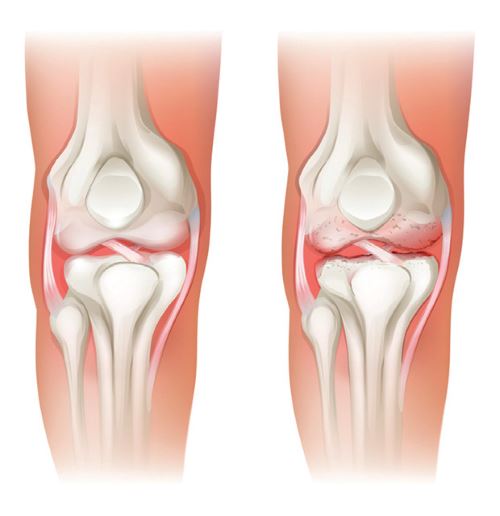

Mouvements douloureux, gonflements, raideurs… à partir de 50 ans, les problèmes articulaires apparaissent. Main, poignet, genou, hanche sont autant de zones touchées par l’arthrose et la polyarthrite. Pour soulager les symptômes, l’harpagophytum se distingue comme étant un antiinflammatoire incontournable.

Ménagez vos articulations

La première règle importante : ne forcez jamais sur une articulation en souffrance ! Dans le cas d’une poussée d’arthrose d’une articulation portante (hanche, genou, cheville), le repos est essentielle pour soulager l’arthrose, le temps de permettre au cartilage de se reconstituer.

Ménagez vos articulations

La première règle importante : ne forcez jamais sur une articulation en souffrance ! Dans le cas d’une poussée d’arthrose d’une articulation portante (hanche, genou, cheville), le repos est essentielle pour soulager l’arthrose, le temps de permettre au cartilage de se reconstituer. Pour ménager vos articulations arthrosiques, pensez à vous aider d’une béquille si nécessaire et d’un caddie pour les courses afin de soulager vos articulations de lourdes charges.